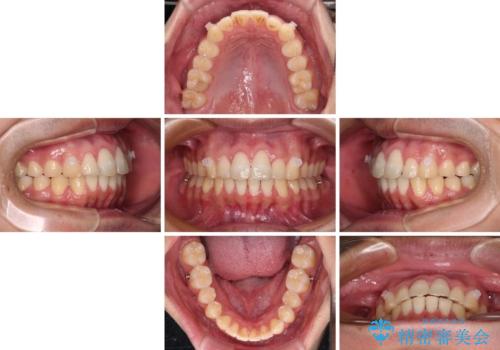

- 上下前歯のデコボコと、それに伴う出っ歯を気にして来院された患者様です。

インビザラインによる上下歯列の側方拡大と後方移動、IPR(歯と歯の間を削る)にるスペースの獲得により歯列を整えることとしました。

歯と歯の間を削ることでうまくスペースコントロールでき、また、毎日22時間以上しっかりとマウスピースを装着していただいたので、スムーズに治療が進みました。

治療途中で転勤となり、遠方からの通院となったため、来院間隔空いてしまいましたが、2年間で終えることができました。